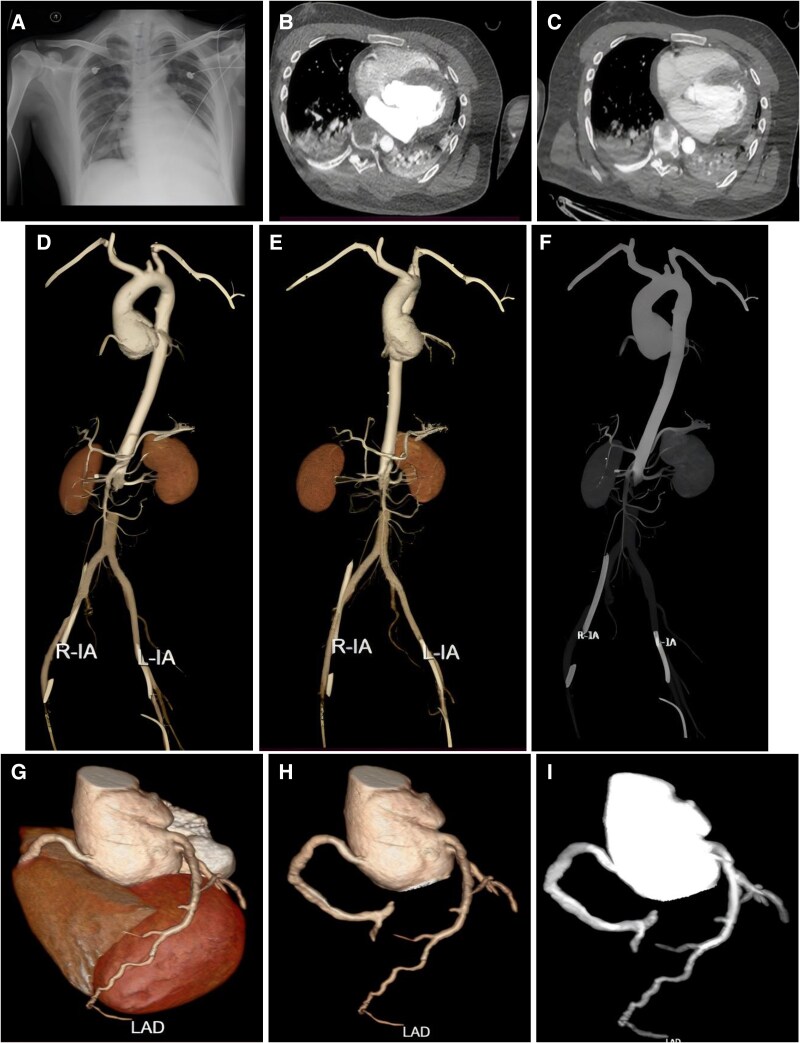

Case summary: An 18-year-old male with suspected Marfan's syndrome presented to our hospital with sudden onset of anterior chest pain without obvious trigger with nausea and vomiting for 10 h, supported by ECMO. His laboratory tests showed leucocytosis, elevated troponin, and creatine kinase. The electrocardiogram showed acute high lateral and extensive anterior wall myocardial infarction. On the second day of admission, he underwent CTA to rule out extensive aortic coarctation and coronary stenosis and found inhomogeneous enhancement of the myocardium and abnormal patchy enhancement of the epicardium, which was considered to be FM. The patient was then treated with methylprednisolone and human immunoglobulin, and his symptoms and laboratory markers improved markedly after a few days.

Discussion: The diagnostic process in this case highlights the challenge of recognizing FM in the context of complex cardiovascular disease. Extracorporeal membrane oxygenation-supported CTA of the aorta combined with computed tomography (CT) cardiac coronary imaging provided an important basis for diagnosis, helped rule out other potential aetiologies, suggested the possibility of myocarditis, and contributed to the patient's optimal therapy.